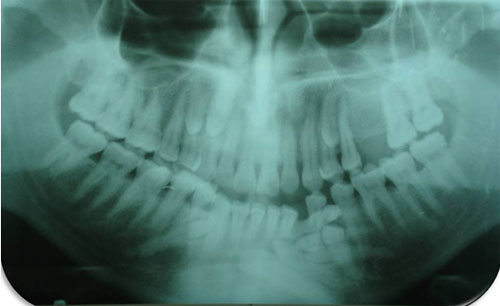

Radiográficamente se observaron 3 imágenes radiopacas compatibles con unidades dentarias incluidas, localizadas en ambos lados del maxilar con apariencia radiográfica de caninos y premolares, por otra parte, en la mandíbula se observaron adicionalmente 6 unidades dentarias incluidas con anatomía similar a los descritos en el maxilar (Fig. 2). Los exámenes de laboratorio revelaron niveles dentro de los parámetros normales y no evidenciaron relación con algún síndrome.

Fig 2

Radiografía panorámica del paciente en estudio, que muestra la presencia de múltiples órganos dentarios ubicados tanto en la arcada inferior como en la superior